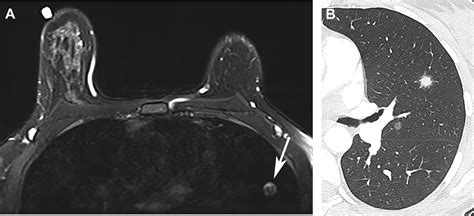

A lung nodule is defined as a growth measuring less than 3 centimeters in diameter. If the growth is larger than 3 centimeters, it is typically classified as a lung mass, which requires a more urgent diagnostic approach. These nodules can be caused by various factors, including old infections, inflammation, or scar tissue. While the term "lung nodule" might sound alarming, it is important to remember that they are often incidental findings discovered during scans performed for completely unrelated reasons, such as a routine physical or after a minor injury.

Determining whether a nodule requires treatment depends on its appearance, size, and your personal medical history. Physicians use several criteria to assess the risk of malignancy. For example, solid nodules with smooth borders are generally less concerning than those with irregular or "spiculated" edges. The following table summarizes how medical professionals categorize risk factors associated with these findings.

| Appearance | Smooth, well-defined | Irregular, spiculated |